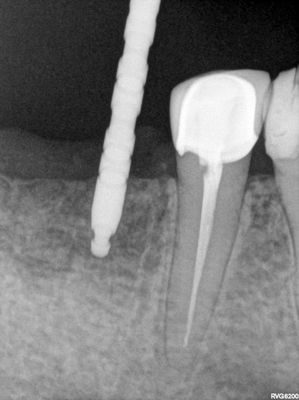

relatively straight forward implant placement, some bone expansion and countersinking. buccal bone thin, grafted with sticky bone from allograft folloewd by collagen mmebrane soaked in prf fluid, additional fibrin membrane used